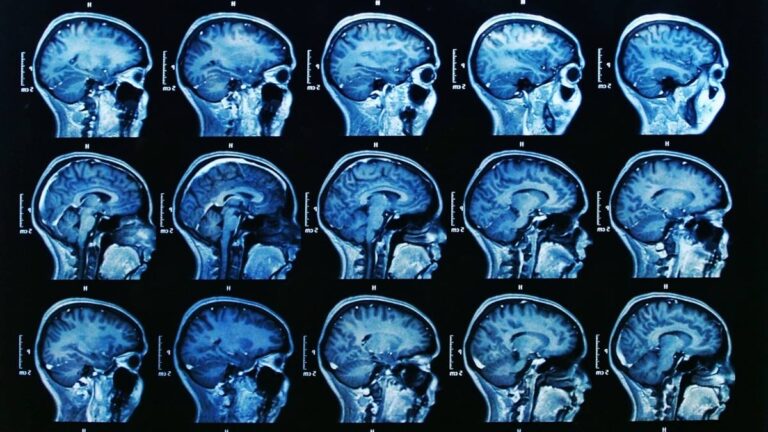

Your hippocampus—the memory center of your brain—is under attack from cortisol, your stress hormone. Think of your hippocampus as a garden. Cortisol is acid rain. A little rain helps plants grow. Too much kills everything.

When stress becomes constant, cortisol floods your brain daily. This physically shrinks your hippocampus. Research shows chronic stress can reduce hippocampal volume by up to 20%. That’s real, measurable damage. Dr. Robert Sapolsky, a leading neuroscientist, spent decades proving that stress literally changes brain structure.

Your amygdala (your alarm system) takes over during stress. It hijacks your thinking brain. Scientists call this “amygdala hijack.” When this happens, your brain prioritizes survival over memory. That’s why stress-induced memory problems feel so sudden and complete.